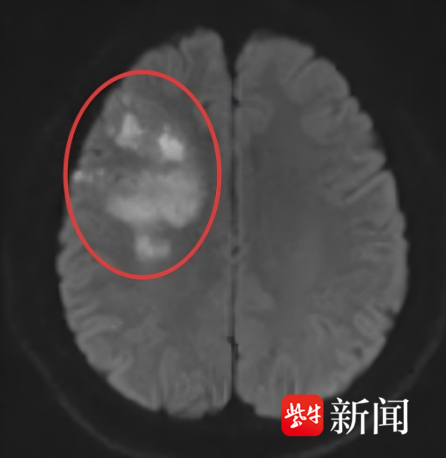

小潘(化名)今年29岁,2周前的早晨起床时突然出现头痛,然后出现视物模糊,口角歪斜,自己服用了布洛芬止痛,效果不明显,随后来到当地医院,一查头颅核磁竟然提示:多发急性脑梗死。

医生在接诊时,捕捉到几个关键信息:小潘体重115公斤,平时爱吃不动,有吸烟习惯,血压偏高却从未干预。入院后再仔细检查示小潘的右侧大脑中动脉斑块致管腔狭窄,右侧大脑半球缺血。

右侧大脑半球急性脑梗

右侧大脑中动脉狭窄